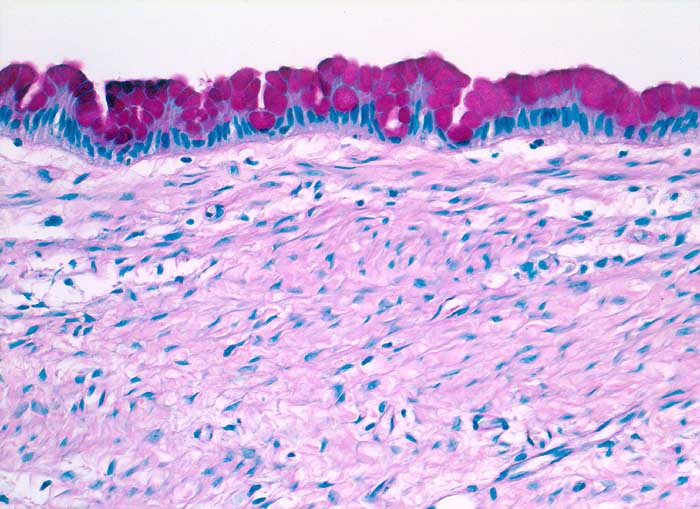

PathoPic – image database / PathoPic ID 5392 - Muzinöses Zystadenom

Muzinöses Zystadenom

Die Zyste ist ausgekleidet von schleimbildenden Zylinderzellen ohne Atypie.

Schleim++

Schleimbildende Zylinderzellen(+)

Da hochdifferenzierte muzinöse Karzinome bisweilen kaum Atypien aufweisen, ist die sorgfältige Untersuchung des Operationspräparates notwendig (mindestens 1 Block pro cm Tumordurchmesser)

Histologie

200